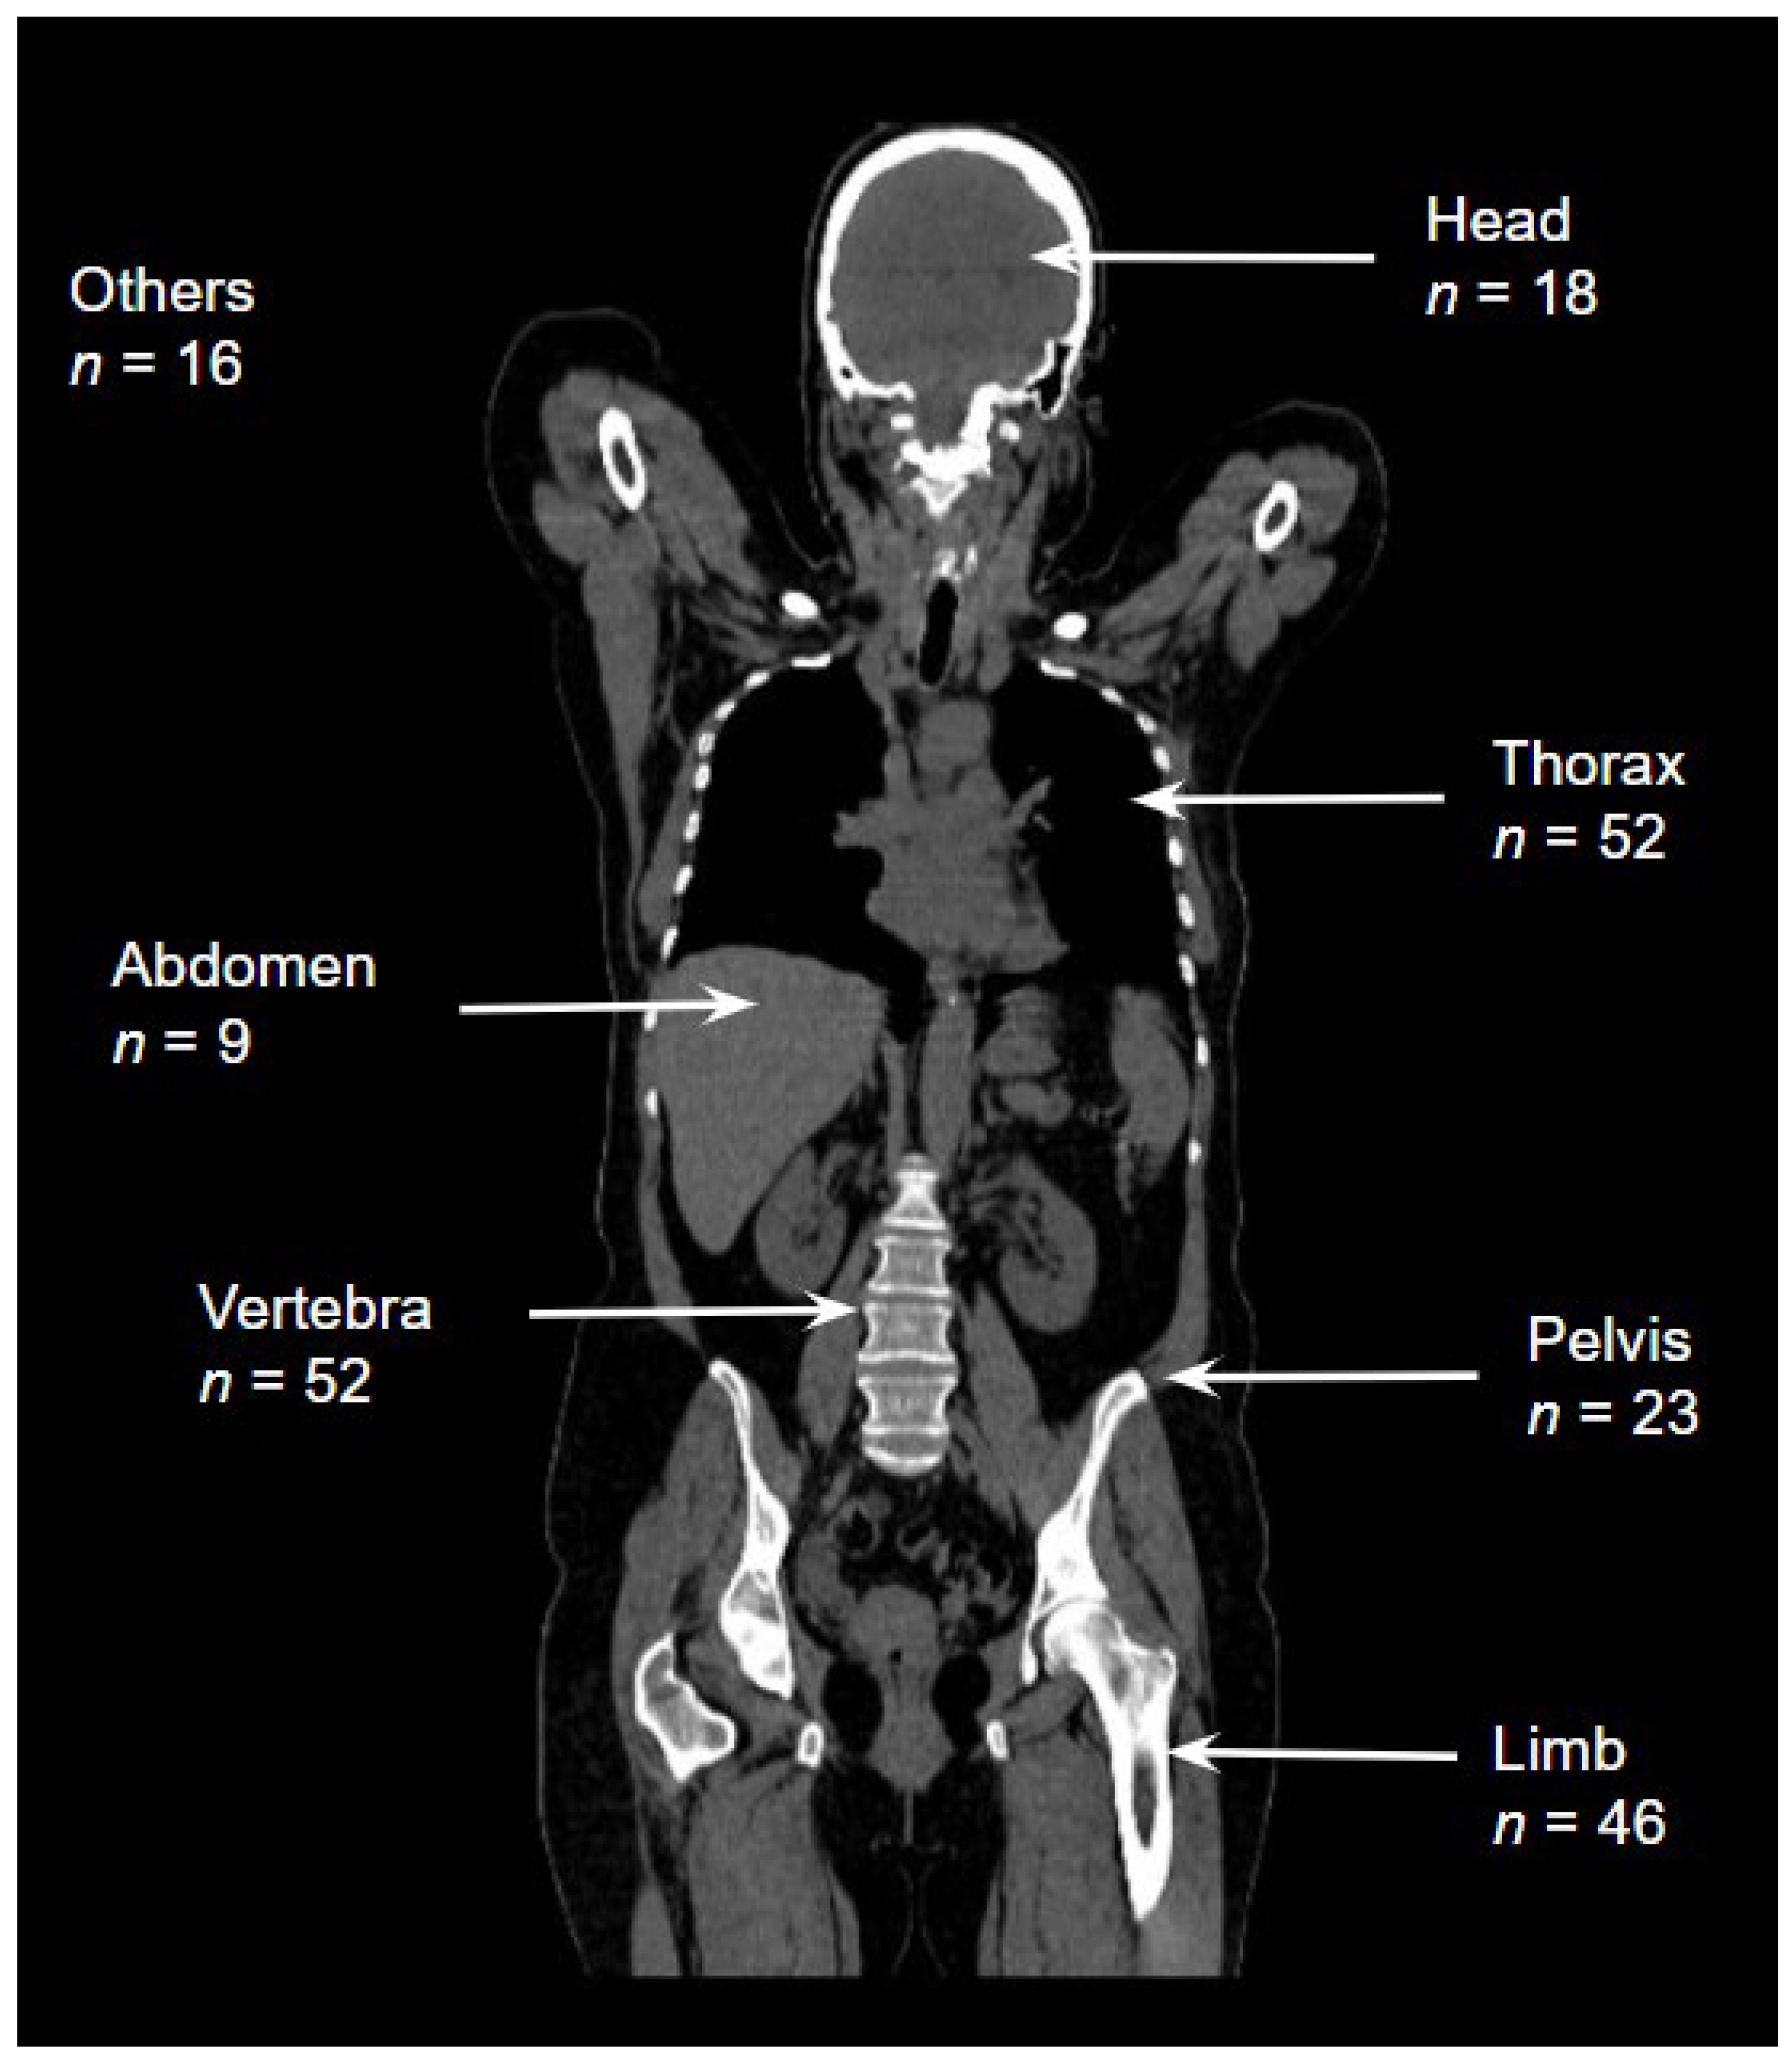

| 0–17 Age (n = 19) | ≥18 Age (n = 141) | All Ages (n = 160) | p | ||||

|---|---|---|---|---|---|---|---|

| Finding + n (%) | Finding − n (%) | Finding + n (%) | Finding − n (%) | Finding + n (%) | Finding − n (%) | ||

| Thorax | 7 (36.8) | 12 (63.2) | 45 (31.9) | 96 (68.1) | 52 (32.5) | 108 (67.5) | 0.667 |

| Vertebra | 3 (15.8) | 16 (84.2) | 49 (34.8) | 92 (65.2) | 52 (32.5) | 108 (67.5) | 0.098 |

| Limb | 5 (26.3) | 14 (73.7) | 41 (29.1) | 100 (70.9) | 46 (28.7) | 114 (71.3) | 0.803 |

| Pelvis | 1 (5.3) | 18 (94.7) | 22 (15.6) | 119 (84.4) | 23 (14.4) | 137 (85.6) | 0.228 |

| Head | 5 (26.3) | 14 (73.7) | 13 (9.2) | 128 (90.8) | 18 (11.3) | 142 (88.7) | 0.027 |

| Abdomen | 1 (5.3) | 18 (94.7) | 8 (5.7) | 133 (94.3) | 9 (5.6) | 151 (94.4) | 0.942 |

| Others | 1 (5.3) | 18 (94.7) | 15 (10.6) | 126 (89.4) | 16 (10.0) | 144 (90.0) | 0.463 |